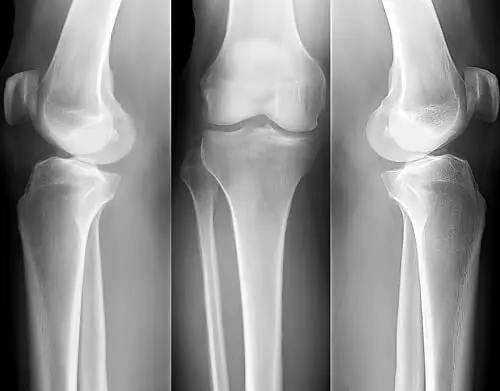

Remedios caseros para la osteoporosis

La mejor manera de luchar contra la osteoporosis es fortalecer los huesos, no importa cuál sea tu edad.